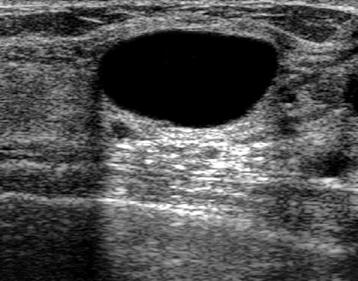

The target dataset was developed from 35 breast ultrasound scans that were segmented by an image-processing expert with extensive experience in breast lesion segmentation (the second author). The images, collected from the Web, are of different dimensions, ranging from to pixels (Figure 3, images resized for sake of illustration). These are the same images used to introduce EFIS originally [1].

Ultrasound images are generally difficult to segment, primarily due to the presence of speckle noise and low level of local contrast. It should be noted that the segmentation of ultrasound actually does require a complete processing chain, (including proper preprocessing and post-processing steps). However, the purpose of using these images was solely to demonstrate that the accuracy of the segmentation can be increased with the application of SC-EFIS.